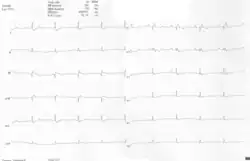

Outras anormalidades que podem ser vistas no ECG incluem (1) sinais de dilatação do átrio direito, ou ondas P espiculadas e alargadas(ondas P 'Himalayan'); (2) Bloqueio atrioventricular de primeiro grau que se manifesta como um intervalo P-R prolongado; (3) complexos QRS de baixa amplitude nas derivações precordiais direitas; (4) bloqueio do ramo direito atípico; (5) inversão de onda T em V1-V4 e ondas Q em V1-V4 e D2, D3 e aVF.[5]